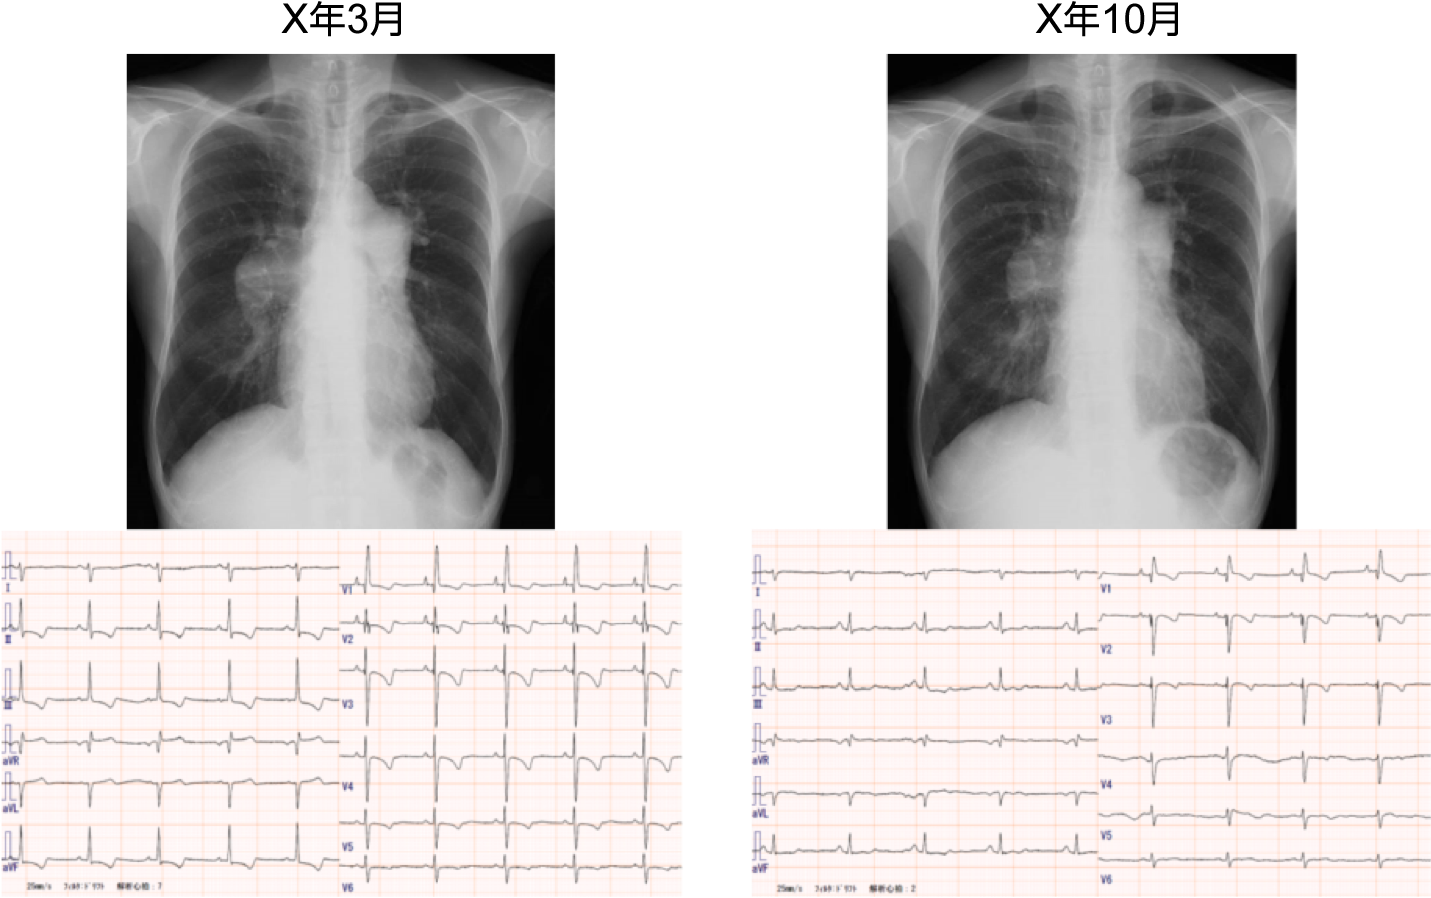

症例1:図1 治療前と治療後の胸部X線と心電図の変化

X線上心陰影は縮小し、心電図上も右室負荷所見が改善している。

症例1:図2 治療前と治療後の心エコー所見

心エコー上も右室の拡大および心室中隔の扁平化が改善している。